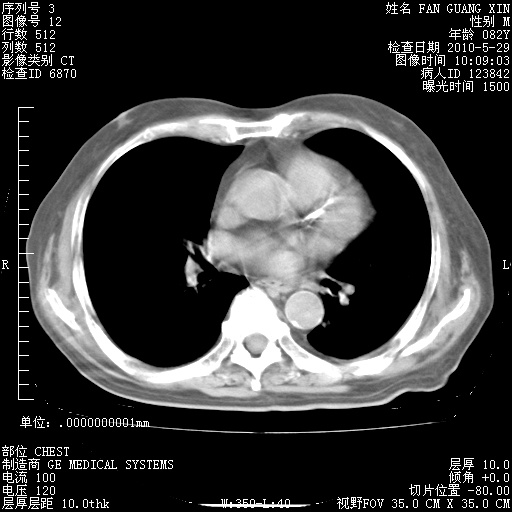

还需要哪些辅助检查?我们医院排除真菌感染没有任何检验方法,胸片好像能够排除肺部真菌感染。

补充:ENA化验全部阴性。免疫五项(IgG、IgA、IgM、C3、C4)只有C4略高。

CD3+ T细胞/淋巴细胞 46% (参考值50.00~84.00%)

CD3+CD4+ T细胞/淋巴细胞 21% (参考值27.00~51.00%)

CD3+CD8+ T细胞/淋巴细胞 25% (参考值15.00~44.00%)

CD3+CD4+ T细胞/CD3+CD8+ T细胞 0.84 (参考值0.71~2.78)

T细胞亚群是治疗5天采血。